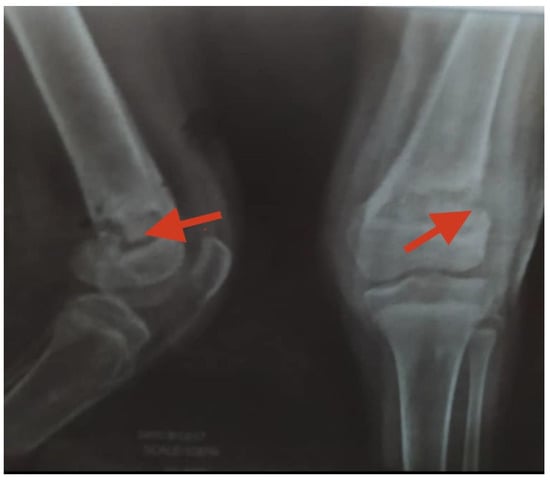

Aseptic necrosis of the femoral head is also a common complication of fractures in adolescents with sickle cell anemia as evident in our patient in Figure 5. Another common bone involvement in sickle cell disease patient is osteonecrosis. Osteonecrosis in sickle cell patients tends to affect a larger bone surface area than osteonecrosis due to other etiologies [18]. According to several works of literature, the increased risk of osteonecrosis of the femoral head in our patient group could be linked to an overall reduction in bone mineral density and marrow hyperplasia compared to the general population [18,19].

Figure 5. Plain radiograph showing avascular necrosis of the bilateral femoral head (black arrows). Commonly seen in sickle cell disease patients due to poor blood circulation from the disease condition.